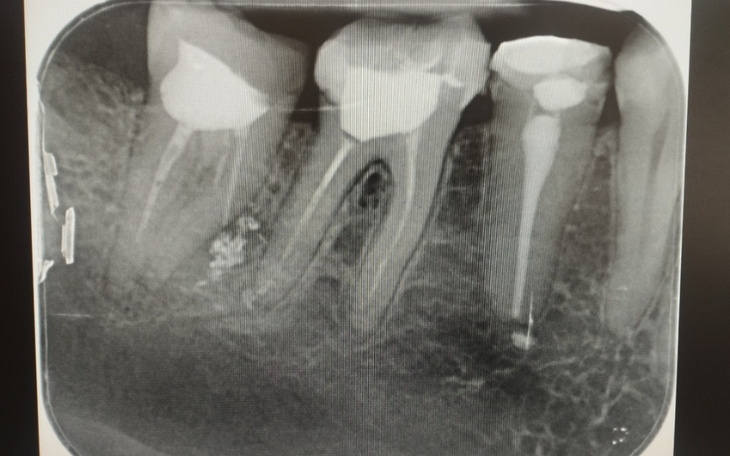

Nazywam się Dorota i na początku roku zaczął mnie boleć ząb i cały policzek, okazało się, że moja poprzednia dentystka źle wypełniła kanał (co można zobaczyć na zdjęciu) w wyniku tego musiałam wyrwać zęba, a jak wiadomo usługi stomatologiczne nie są tanie. Dentystka, która mi to zrobiła przyznaje się że źle wypełniła i może oddać mi jedynie 350zł. Ta kwota nawet nie pokrywa naprawy ostatniego zęba. A dzięki niej muszę jeszcze kilka naprawić. Nie stać na adwokata, żeby móc starać się o odszkodowanie. A też nie wiadomo czy by się udało... Dlatego założyłam zbiórkę, mam nadzieję że dobre duszę pomogą mi i w końcu wyleczę zęby i moje węzły chłonne wrócą do normalności i przestaną boleć 🙏